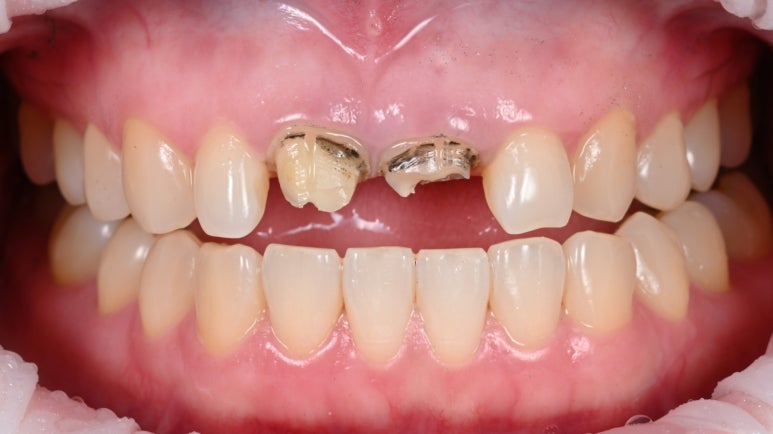

2. 기존 크라운 제거 & 재신경치료 시작

기존 크라운을 제거하고 내부 충치를 정리하며 재신경치료를진행했습니다.

25.08.11

25.08.11 기존 크라운 제거 후 모습